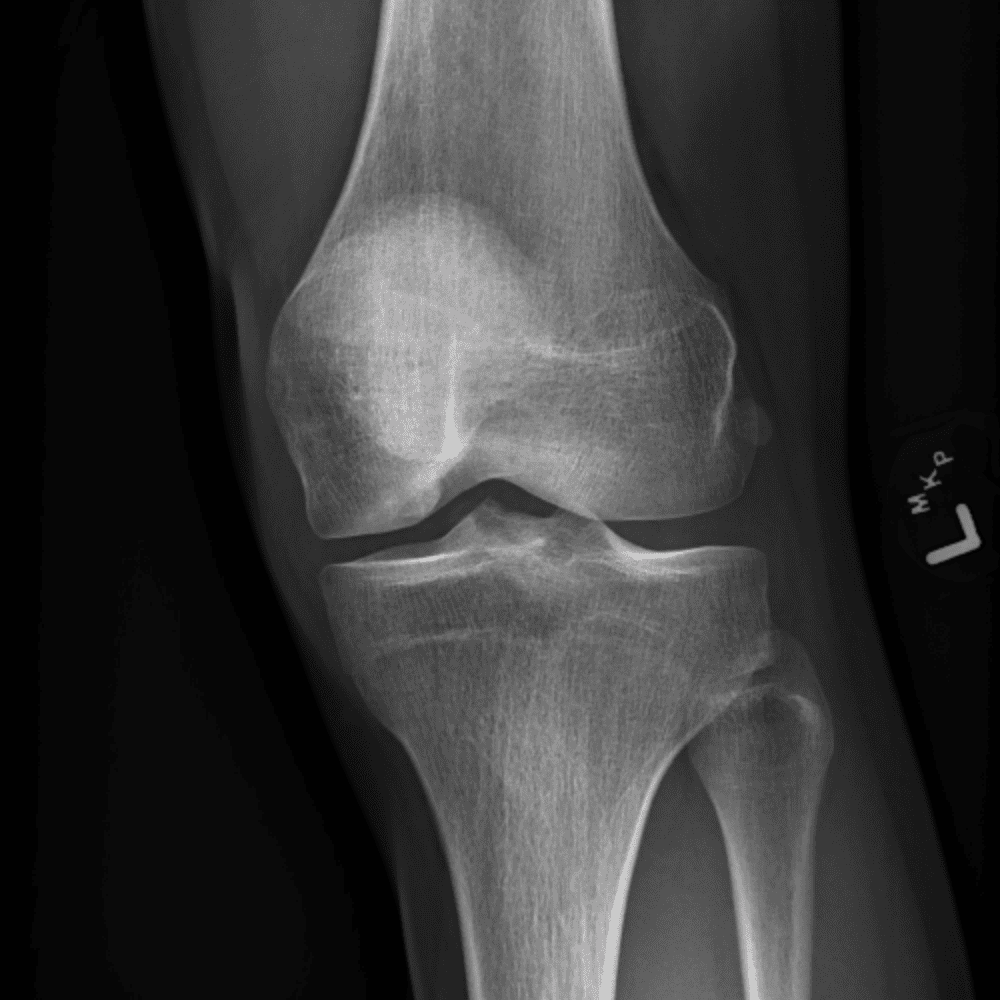

Simula o plantão incluindo casos sutis ou difíceis e alguns normais.